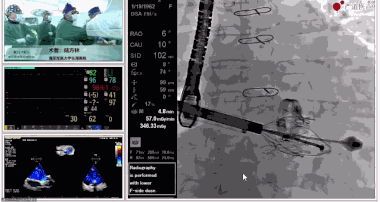

陸方林教授分享的是一例極重度三尖瓣返流的患者采用健世科技(LuX-Valve®)經(jīng)導(dǎo)管三尖瓣置換系統(tǒng)進(jìn)行的手術(shù)直播演示。此例患者為69歲女性,入院前17年行二尖瓣機(jī)械瓣置換術(shù),術(shù)后長(zhǎng)期服用華法林抗凝,既往“2型糖尿病”病史5年,“雙下肢水腫”3年。3個(gè)月前患者出現(xiàn)腹脹、雙下肢水腫,伴活動(dòng)后暈厥,伴黃疽、皮膚濕癢、牙齦出血,癥狀持續(xù)加重,遂入院治療。入院后行心臟CT、心臟超聲檢查,提示:“三尖瓣關(guān)閉不全(極重度),二尖瓣置換術(shù)后,心功能III級(jí)”。徐志云、陸方林微創(chuàng)三尖瓣置換團(tuán)隊(duì)對(duì)該患者的病情進(jìn)行了充分的評(píng)估和討論。由于患者有開胸二尖瓣置換手術(shù)史,且病史時(shí)間長(zhǎng),同時(shí)存在相關(guān)合并癥,傳統(tǒng)外科手術(shù)風(fēng)險(xiǎn)極高(STS評(píng)分:8.315%),最終決定采用三尖瓣LuX-Valve®瓣膜系統(tǒng)對(duì)患者進(jìn)行治療。

▲瓣膜植入前右心室造影

▲瓣膜植入后右心室造影

在手術(shù)直播中瓣膜植入過程不到10分鐘,手術(shù)獲得圓滿成功,充分體現(xiàn)徐志云、陸方林團(tuán)隊(duì)技術(shù)精湛,團(tuán)隊(duì)協(xié)作默契及器械的優(yōu)越性。